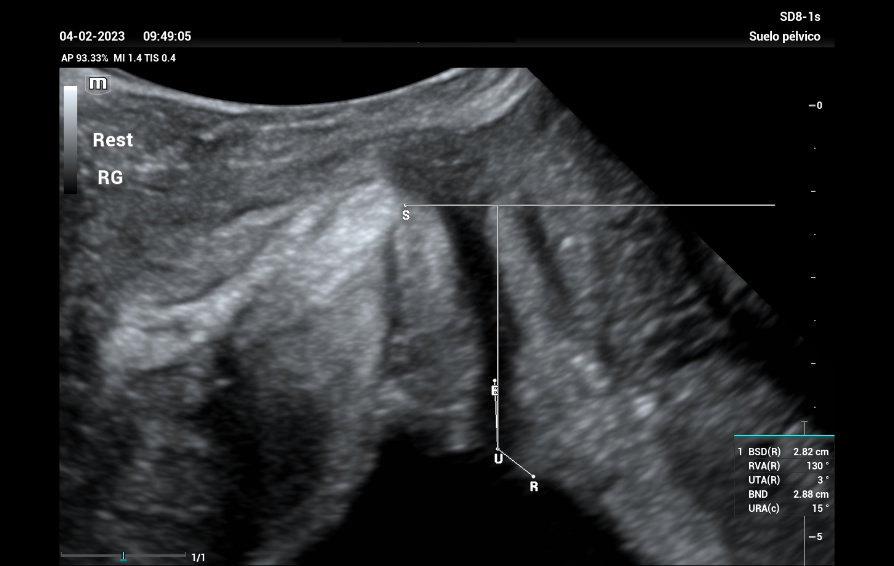

A study was carried out with filling bladder of 300 ml. The reference line is set at the inferior margin of the symphysis pubis, giving a total result of Bladder neck descent (BND) of 28mm, a UTA angle of 3? and a beta angle (RVA) of 130? (Figure 1), both within normal parameters, we performed the Valsalva maneuver showing a 26mm descent, and after maneuvering of Valsalva (Figure 2) a UTA angle of 13? (10? rotation) is observed, RVA of 98?.